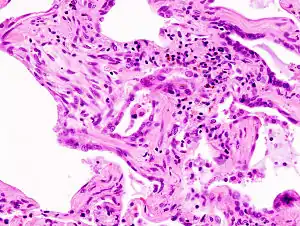

| End-stage pulmonary fibrosis of unknown origin, taken from an autopsy | |

Prolonged ILD may result in pulmonary fibrosis, but this is not always the case. Idiopathic pulmonary fibrosis is interstitial lung disease for which no obvious cause can be identified (idiopathic) and is associated with typical findings both radiographic (basal and pleural-based fibrosis with honeycombing) and pathologic (temporally and spatially heterogeneous fibrosis, histopathologic honeycombing, and fibroblastic foci).